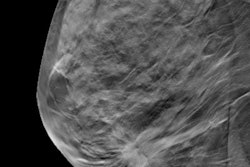

Adding screening digital breast tomosynthesis (DBT) to annual mammography is cost-effective when compared with mammography alone -- particularly in women between the ages of 40 and 49, according to a new study published online August 22 in the American Journal of Roentgenology.

Kalra's team designed a model for annual screening with both tomosynthesis and 2D mammography for a population of women ages 40 to 74 across all breast tissue densities. The group defined model parameters from a multi-institutional study of more than 450,000 patients, institutional data from 13,000 patients, a literature review, and Medicare reimbursement rates. The base case for the model was a 56-year-old woman presenting for an annual screening exam (AJR, August 22, 2016).